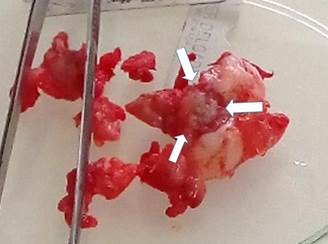

In order to perform the ostectomy, an assistant turned the limb outwards until the patella is directed upwards; this maneuver produced the dislocation of the joint. The exeresis was performed with an osteotome and an impactor. The line of ostectomy belonged to a straight line between the junction of the femoral neck and the third trochanter (Figure 3).

Figure 3 Surgical piece after the femoral head and neck exeresis. The tissue is multifragmented with irregular fibrous tissue, a region of collapsed and necrotic articular cartilage (white arrows), as well as subchondral cracks (black arrows) is evident in the femoral head.

To perform the ostectomy, an assistant turned the limb out until the patella was directed upwards; this maneuver caused dislocation of the joint. The exeresis was performed with an osteotome and an impactor. The ostectomy line corresponded to a straight line between the junction of the femoral neck and the third trochanter (Figure 4).